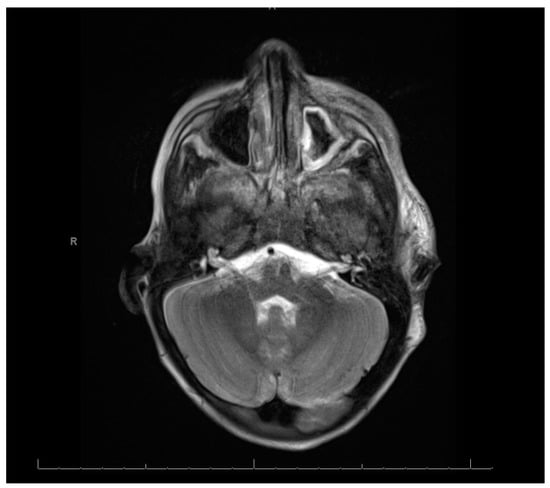

Swabs: A nasopharyngeal swab for a viral multiplex polymerase chain reaction (PCR) was negative. A nasopharyngeal swab for coronavirus disease was negative. A wound swab of the pus aspirate from the oral cavity revealed Gram-negative rods found to be Fusobacterium necrophorum. The identification and susceptibility of causative microorganisms were performed by a VITEK 2 compact system and antibiotic susceptibility testing was interpreted using internationally recognized standards, those established by the Clinical and Laboratory Standards Institute (CLSI) [7]. Cerebrospinal Fluid (CSF): The CSF was clear and colorless. The total WBC was 72 /mm3. The neutrophil content was 94%, the lymphocyte content was 4%, and the monocyte content was 2%. The level of protein in the CSF was high at 0.8 mg/dL, and the glucose value was 2.2 mg/dL. The patient’s gum pus was positive for methicillin-resistant Staphylococcus aureus (MRSA). A blood culture showed Gram-positive cocci in clusters. However, there was no history of any family member with MRSA and the patient was not admitted to the hospital before this admission. Echocardiography: Normal. Electroencephalogram: The electroencephalogram indicated a subclinical seizure. Brain and neck computed tomography (CT) with contrast findings is shown in Figure 1 and Figure 2.

Figure 1.

Brain and neck computed tomography with contrast.

Figure 2.

Brain and neck computed tomography with contrast (cross-sectional view).

Figure 1 and Figure 2: (A) Loss of corticomedullary differentiation in the right frontal, parietofrontal, and left parietal lobes, indicating a possible microinfarction. (B) Thrombosis in the right internal jugular vein. (C) Left maxillary and ethmoidal sinusitis. The neck CT showed the following: (A) An enlarged heterogenous left parotid gland containing multiple micro-abscesses, with soft tissue swelling and cervical lymphadenopathy, which could represent an infectious/inflammatory process. (B) Right internal jugular vein thrombosis. (C) Multiple bilateral peripheral lung nodules, suggesting that the differential diagnosis could include septic emboli.